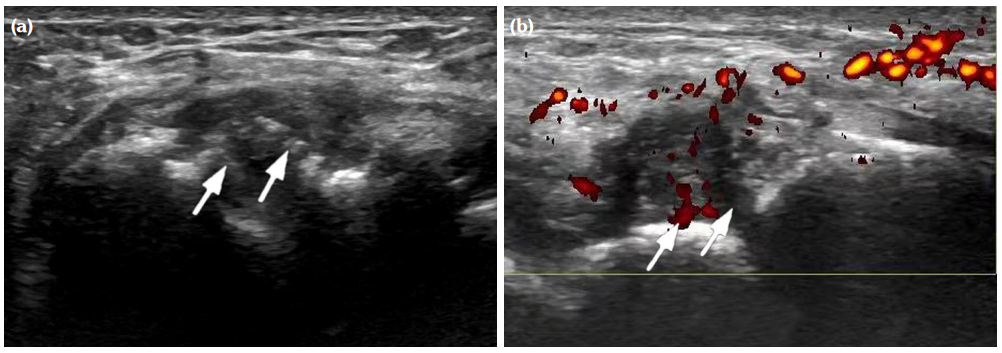

The degree of BE and synovial hyperplasia in SNRA or SPRA is more serious, and the blood flow signal is more abundant. However, the degree of synovial hyperplasia in osteoarthritis was mild, and no obvious blood flow signal was detected (Figures 1, 2, 3 and 4). Magnetic resonance imaging (MRI) studies of SPRA also showed serious BE (Figure 5).

Difference in ultrasound findings among SNRA, SPRA and non-RA groups

Among SNRA, SPRA and non-RA, there was no significant difference in the grades of SH, PD, BE, nor the number of cases of tendinitis and tenosynovitis between the SNRA group and the SPRA group (p>0.05) (Table 3). There were, however, statistically significant differences in the number of cases of SH1, SH3, PD and BE grades between the SNRA and non-RA groups (p<0.001). There was no significant difference in the number of cases of SH2, PD2, tendinitis or tenosynovitis between the SNRA and non-RA groups (p>0.05) (Table 4).